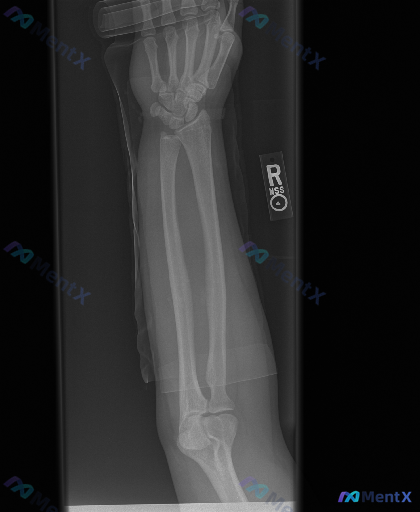

整理到一份右侧前臂X光正位影像的病例资料,先和大家同步目前可见的表现: 1. 骨骼方面:桡骨远端干骺端区域可见骨皮质中断,远折端有向背侧/桡侧移位的迹象;尺骨茎突处也有骨皮质不连续的表现。 2. 关节方面:桡腕关节的正常解剖关系似乎有改变,下尺桡关节区域看起来间隙不太规整。 3. 软组织:桡骨远端周...